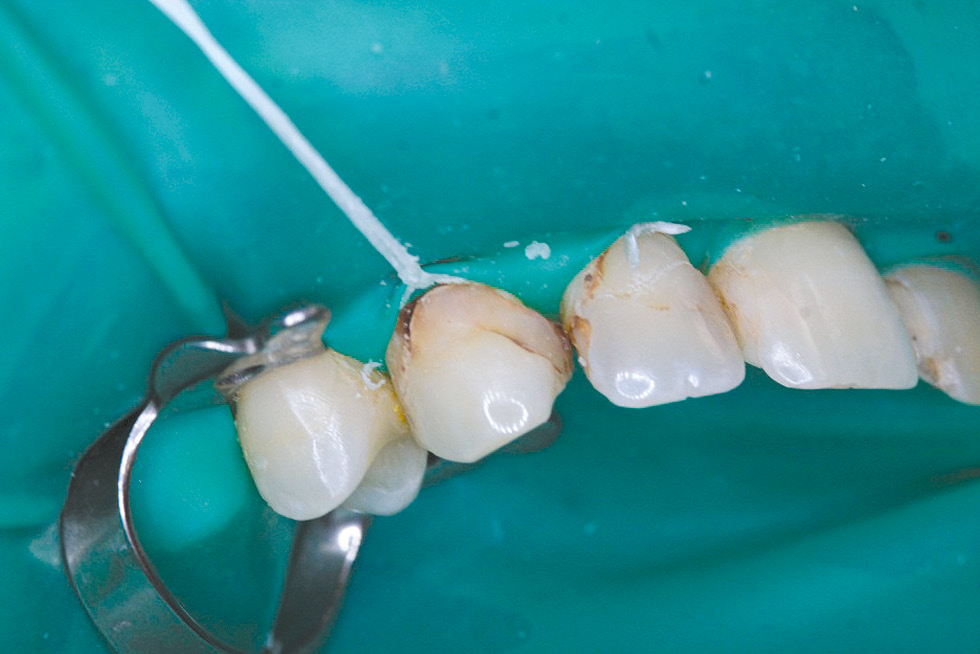

Treatment plan: removal of failed restoration 1.3, direct composite restoration 1.3. Given the significant defects in the hard tissues of the vestibular surface 1.3, it seems important to achieve the maximum possible degree of adhesion of the composite material to the hard tissues of the tooth, therefore, a combination of the adhesive system OptiBond Universal (Kerr) and the composite material OptiBond Universal (Kerr) with the effect of polychromy was used.

Treatment was carried out: under infiltration anesthesia Sol. Articaini–1 ml under water-air cooling, failed 1.3 restorations were removed, the vestibular surface was prepared for the manufacture of a direct composite restoration (Fig. 10). Enamel 1.3 was selectively etched, the OptiBond Universal adhesive system (Kerr) was applied, and direct restoration was performed using the OptiShade nanohybrid universal composite (Kerr) (Fig. 11, 12).

The use of the nanohybrid universal composite "OptiShade" (Kerr) made it possible to optimize the work in this clinical case. This material is presented in three shades (Light, Medium, Dark). To replace enamel and dentin, the Medium shade was used, which, thanks to the color substitution of sixteen shades, made it possible to successfully imitate the enamel and dentin of the tooth in terms of color. Due to the high adaptive characteristics and manipulation properties, the restoration of tooth 1.3 looks aesthetically pleasing. The time spent on restoration was reduced due to the use of a single shade of material.